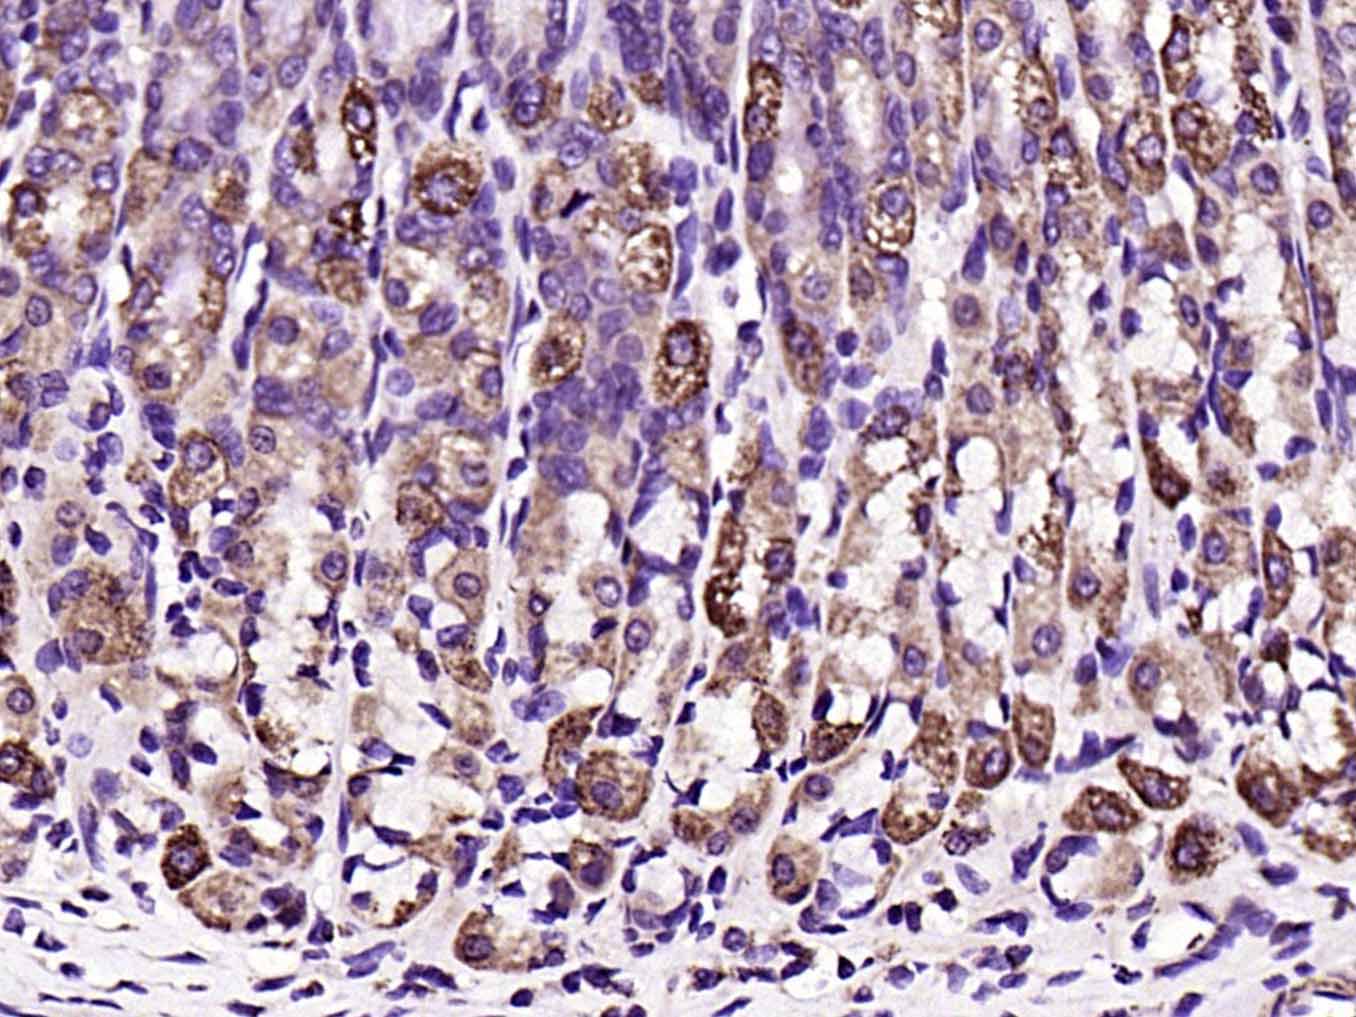

| IHC-P | Human, Mouse, Rat | Rabbit, Pig, Sheep, Cow | 1:100-500 |